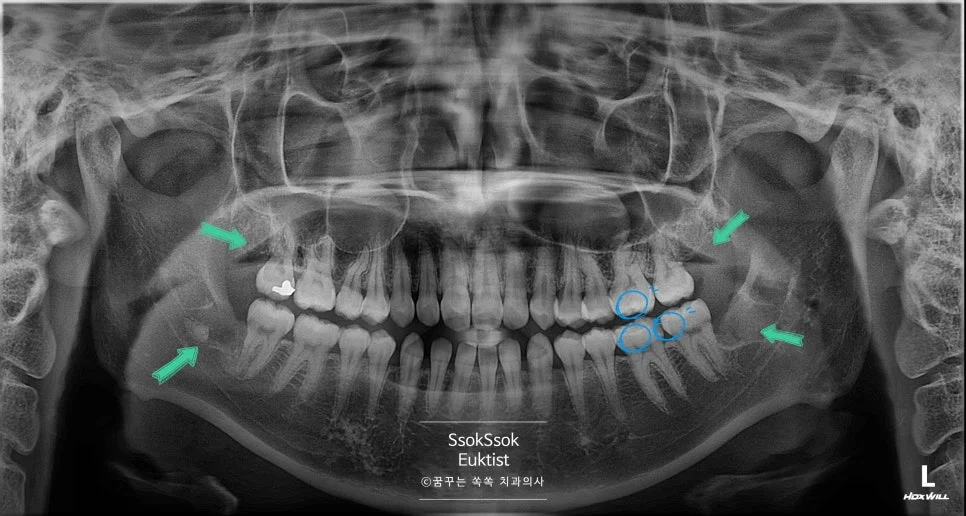

환자분께선 왼쪽 위, 아래 사랑니(좌측 상악 제3대구치와 좌측 하악 제3대구치)가 통증이 심하여 발치를 원하셨습니다.

상악 왼쪽 사랑니 구강 내 사진

파노라마와 CBCT(Cone Beam CT) 촬영 결과, 왼쪽 위 사랑니는 쉽게 발치할 수 있는 사랑니였고, 왼쪽 아래 사랑니의 경우 신경관과 1mm 이내로 붙어 있는 신경 손상의 위험이 있는 매복 사랑니입니다.

그래서인지 왼쪽편 실을 푸는 날, 반대편 사랑니 발치 및 다른 치료도 함께 원하셨습니다.

오른쪽 아래 사랑니의 경우 신경관과 바로 붙어 있습니다.

오른쪽 위 사랑니는 잔존 뿌리 없이 깨끗하게 발치